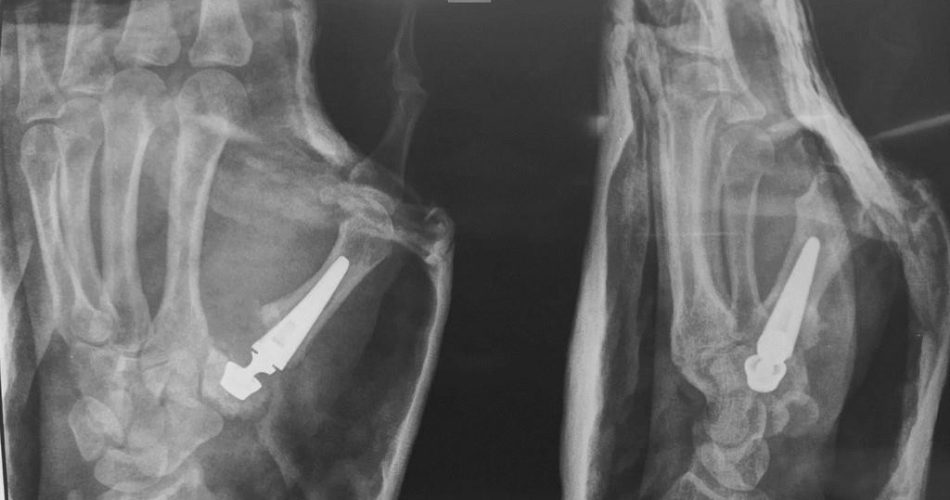

protesi

Una piccola protesi applicata alle articolazioni della mano per eliminare il dolore e conservare il movimento: è attraverso la nuova tecnica chirurgica che per la prima volta al Policlinico di Bari sono stati sottoposti a intervento tre pazienti affetti da artrosi del pollice. Le operazioni di sostituzione totale dell’articolazione trapezio metacarpale del primo dito con una protesi sono state eseguite dall’equipe dell’Unità operativa complessa di Ortopedia e Traumatologia universitaria diretta dal professor Biagio Moretti.

“Nella nostra clinica abbiamo eseguito per la prima volta al Policlinico di Bari interventi di protesi alle piccole articolazioni della mano su tre pazienti affetti da artrosi trapezio metacarpale gravemente invalidante – spiega il dottor Francesco Rifino, medico dell’Unità operativa di Ortopedia e traumatologia del Policlinico di Bari  – finora gli interventi prevedevano diverse tecniche chirurgiche tra cui il blocco dell’articolazione o la rimozione del trapezio deformato che provoca il dolore e l’impotenza funzionale con sua sostituzione attraverso un “gomitolo tendineo”, tutte tecniche mirate a ridurre la problematica attraverso soluzioni palliative. Grazie alla nuova tecnologia,  abbiamo sostituito le piccole articolazioni malate e deformi con mini-protesi che ripropongono la biomeccanica articolare originale allo scopo di eliminare il dolore e restituire al paziente una funzione simile a quella esistente in epoca precedente all’insorgenza della patologia. È una tecnica che si affianca alle altre ma rappresenta un’arma in più per consentire ai pazienti di conservare i movimenti senza avere nessuna restrizione”.

Dopo l’intervento, il paziente viene immobilizzato per pochi giorni e deve seguire successivamente un percorso riabilitativo. “Il Policlinico di Bari rappresenta un punto di riferimento anche per la chirurgia della mano e in particolare per la patologia artrosica di questo distretto, una malattia degenerativa delle piccole articolazioni che diventa disabilitante perché causa una limitazione funzionale importante mentre gesticoliamo, afferriamo gli oggetti, e durante le funzioni elementari della vita di ogni giorno. Queste nuove soluzioni chirurgiche che nella clinica ortopedica abbiamo iniziato ad utilizzare, rappresentano il prodotto delle innovazioni tecnologiche che permettono di riprodurre su scala ridotta protesi articolari finora utilizzate per le grandi articolazioni come il ginocchio, l’anca e la spalla. Questi pazienti vengono seguiti presso un ambulatorio dedicato, in considerazione della peculiarità delle problematiche cliniche e riabilitative connesse alla chirurgia ricostruttiva impiegata” spiega il professor Biagio Moretti, direttore dell’Unità operativa di Ortopedia del Policlinico di Bari.